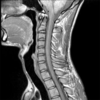

‎请注意,本程式以来自海外的英语放射诊断科视频,提供各种诊断个案,暂时没有提供中/英文字幕。 诊断过程需要优秀的临床技巧,但是,正确应用不同的造影工具,能大大帮助鉴别诊断或证实临床的怀疑。这不应该是”渔翁撒网”式的策略,以一系列的诊断调查表,取代临床技巧。相反,诊断影像的知识,能大大提高诊断过程的水平。 随着科技日新月异,新型医疗仪器不断推陈出新,让医疗专业人员在疾病诊断上,提供极大的帮助。除往日的X光,计算机X射线断层造影术(Computed Tomography, CT),B超(Ultrasound)外,新型的工具包括磁共振显像(MRI),核医学(Nuclear Medicine, NM…